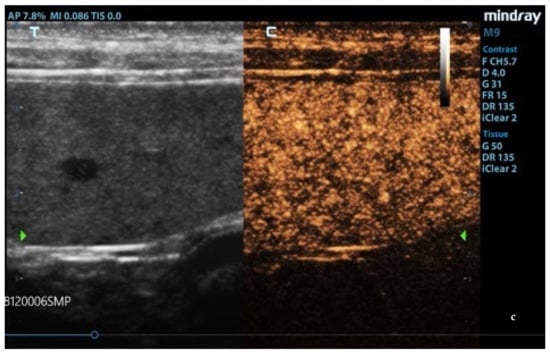

3.2. B-Mode Ultrasonography

Splenic enlargement was found in 11/22 (50%) leishmaniotic patients. Overall, 7/11 (63.6%) had diffuse parenchyma abnormalities, which were always accompanied by an increased size (Figure 1). Parenchyma had a moth-eaten appearance in 4/7 and a marbled appearance in 3/7. In the remaining four, spleen was subjectively reported to be of a larger size than normal but with a normal echotexture. A positive correlation with the clinical stage of disease was detected for splenic enlargement (r = 0.634; p = 0.036) and diffuse parenchymal alterations (r = 0.655; p = 0.047). The correlation between ultrasonographic alteration and splenic quantitative PCR showed a low positive effect (r = 0.06; p = 0.779). Conversely, there was no correlation between spleen enlargement and echotexture with lymph node parasite load (r = 0.26; p = 0.573, r = −0.329; p = 0.4705, respectively) and IFAT title (r = 0.33, p = 0.1413, r = −0.38; p = 0.09, respectively). In none of the three dogs negative for L. infantum were splenic enlargement or abnormalities of echotexture detected. Upon CPD examination, flow signals were detected in both normal appearance and in moth-eaten and marbled spleens; under careful observation, CPD frames in moth-eaten spleens showed the absence of flow in the more visible hypoechoic foci (Figure 2).

Ultrasound patterns of the spleen in L. infantum-infected dogs: (a) moth-eaten pattern and (b) marbled pattern. F: probe’s frequency; D: distance; G: gain; FR: frame rate; DR: dynamic range; AP: acoustic power; MI: mechanical index; TIS: tissue imaging specific; M9: ultrasound system. Green arrow: ultrasound focal point.

Honeycomb, Swiss-cheese-like, and moth-eaten are the metaphorical names used to describe the ultrasonographic finding of small hypoechoic nodules throughout the spleen, causing a spotted echotexture that is commonly seen not only in lymphoma and mast cell neoplasia but also in benign conditions (extramedullary hematopoiesis, lymphoid hyperplasia, and pyogranulomatous splenitis) in dogs and cats [34,35,36]. These above-mentioned metaphorical definitions are, however, synonyms. In this study, the B-mode ultrasound examination of the spleen revealed an increase in the size of the organ in half of the subjects with CanL, with diffuse echotexture abnormalities (moth-eaten or marbled) in about 30% of all affected subjects. Interestingly, parenchymal abnormalities were only seen in cases of enlarged spleens, with 63.6% of dogs with splenomegaly presenting one of the two observed patterns. Moreover, these alterations were significantly more frequent in those subjects with a more severe disease, and echotexture abnormalities showed a positive but not significant correlation with splenic L. infantum quantitative PCR. In a previous report, ultrasonographic splenomegaly and honeycomb or inhomogeneous patterns were reported in not dissimilar percentages of dogs; particularly, the authors stressed that the honeycomb appearance had never been previously associated specifically with CanL [12]. In our opinion, the moth-eaten or marbled echostructure aspects of the spleen are compatible with moderate–severe leishmaniosis, and they could be associated with the list of clinical and clinicopathological abnormalities detected in LeishVet stages II–IV. A limitation of our study was the lack of the histological confirmation of the ultrasonography patterns; however, we performed a clinical field study, and the experimental design did not provide for the performance of a splenic biopsy or the sacrifice of the animal after the investigation procedures. This was due to ethical issues involved in taking splenic biopsies from normal dogs and the legal prohibition of sacrificing pets with leishmaniosis in Italy, apart from cases with a poor prognosis associated with a bad quality of life. Thus, only splenic fine needle aspirations were included in the diagnostic evaluation to exclude pathological conditions compatible with the observed diffuse ultrasound changes of the spleen. The absence of a statistically significant correlation between parasite loads and the ultrasound aspect could also have been a consequence of a lower sensitivity of the FNA sampling method due to the risk of getting inadequate (hemodiluted) or unrepresentative samples. In fact, a study performed on spleens obtained after dog culling showed different parasite loads in different areas of the parenchyma [10]. Therefore, we speculate that ultrasonographic findings could reflect the histopathological alterations that have been reported in the spleen of Leishmania-infected dogs and that the disorganization and destruction of the splenic lymphoid tissue are associated with a more severe disease [37,38]. However, we intend to carry out histological examination of the spleens of dogs with leishmaniosis in the case of culling after an ultrasound examination in order to correlate the ultrasound images to the histopathological pictures.